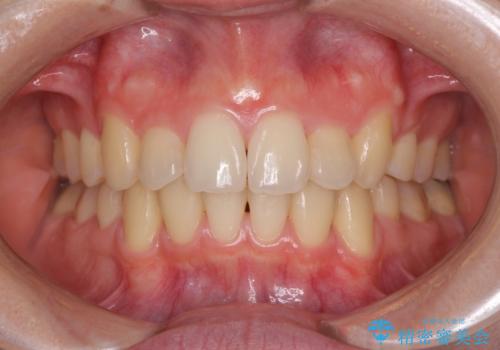

前歯をきれいに整えたい ワイヤー装置での非抜歯矯正